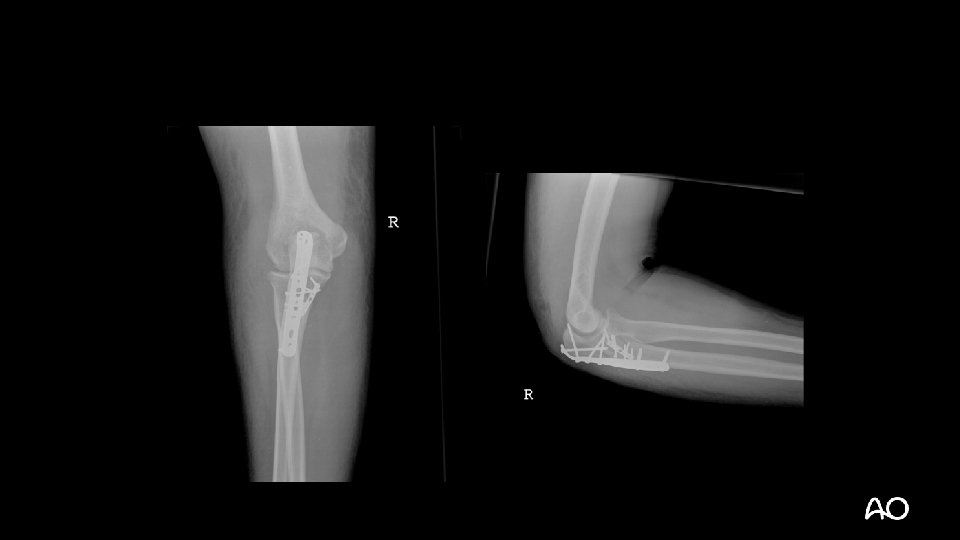

Case 1

Terrible triad fracture dislocation • Historically poor outcomes • Injury “triad”: • Elbow dislocation (often posterior) • Radial head fracture • Coronoid fracture

Terrible triad • Treatment principles: • Repair coronoid/anterior capsular attachment • Repair or replace radial head • Repair LCL • NEVER CREATE MORE INSTABILITY: • Ignore “small” (fleck) coronoid fractures: • These are NOT “avulsion” fractures by brachialis, as radiologists often like to say on their x-ray reads • Resect radial head without replacing it • MCL does not usually need operative repair

Terrible triad—tactic • Kocher approach to elbow (ECU-anconeus interval) • LCL often avulsed from lateral epicondyle: • “Bare epicondyle” • If resecting the radial head, do it now to improve access to coronoid ECU = extensor carpi ulnaris

Terrible triad—tactic • Repair coronoid or anterior capsule: • Suture tunnels through proximal ulna • Screws • Consider medial approach for plating type III coronoid fractures • Complete repair or replacement of radial head • Repair LCL during closure Regan et al (Orthopaedics. 1992; 15: 845– 848)